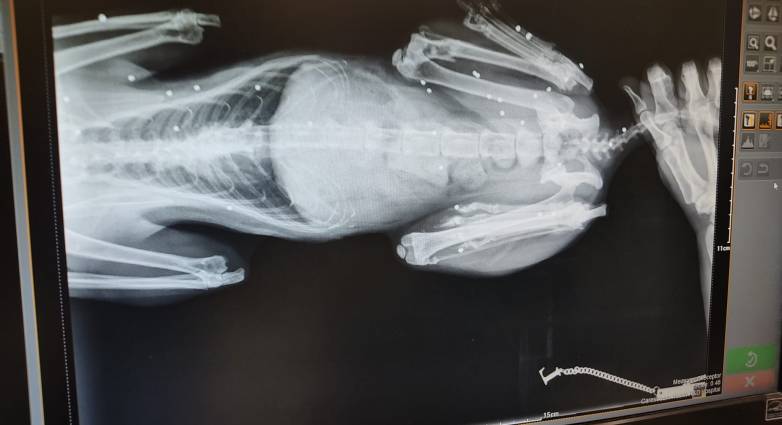

Στην δεξιά φωτογραφία, είναι επίσης η γάτα μου η Ρέα, και αυτό είναι μία ακτινογραφία απ’ το σωματακι της που τραβήχτηκε από τον κτηνίατρο στην Μύκονο πριν τρεις εβδομάδες, έπειτα από ένα μεγάλο ταξίδι αυθημερόν με σκοπό να την φέρω εδώ στην Μύκονο από την Κάτω Αχαΐα , όπου την είχα αφήσει στους γονείς μου να την φροντίζουν τους τελευταίους έξι μήνες.

Ο κτηνίατρος εδώ στην Μύκονο διέγνωσε ότι δέχτηκε πυροβολισμό εξ επαφής και έχει πάνω από 30 σκάγια από αεροβόλο μέσα στο κορμί της. Το γεγονός ότι συνέβη κάτι τέτοιο και η Ρέα ζεί ακόμα, οφείλεται στο ότι ο άνθρωπος που την πυροβόλησε, σύμφωνα με τον κτηνίατρο, δεν γνώριζε καλό σημάδι, με αποτέλεσμα η γάτα μου να επιβιώσει μεν αλλά να έχει μέσα της τα σκάγια.